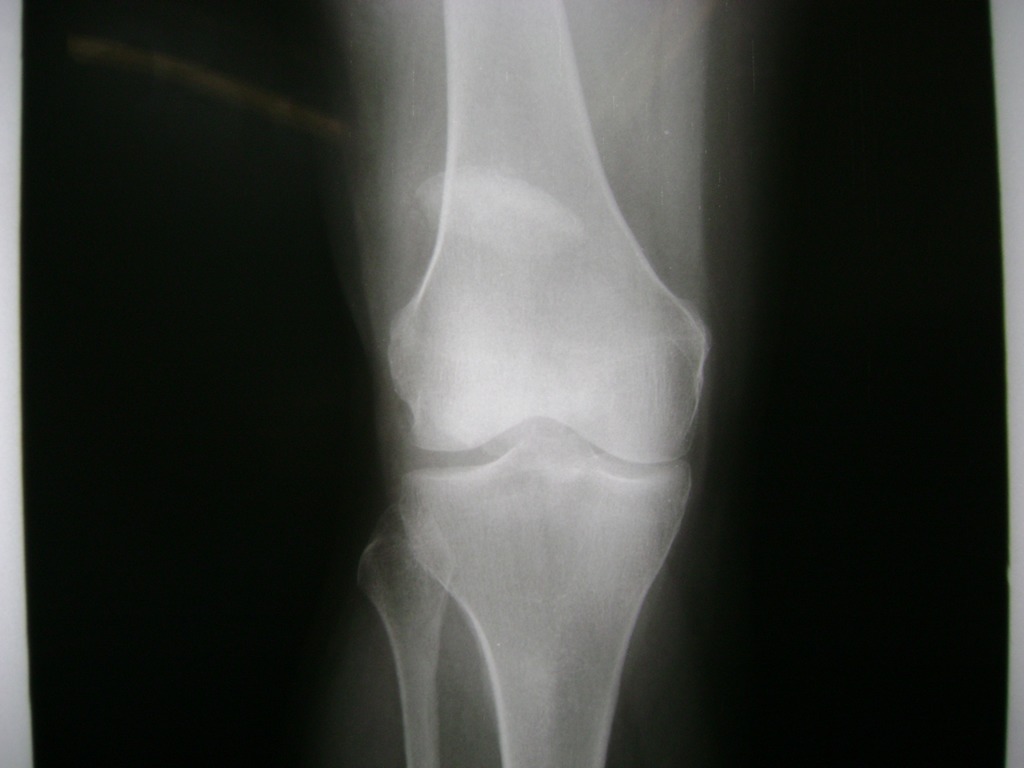

Cirugías de Húmero - Rodilla

La artroscopia de rodilla es un cirugía en el cual la estructura interna de la articulación es examinada ya sea para realizar un diagnostico o para realizar un tratamiento, este procedimiento se realiza utilizando un instrumento parecido a un pequeño tubo llamado artroscopio.